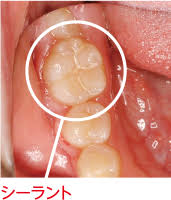

シーラントは歯のかみ合わせの面の溝を埋める処置です。